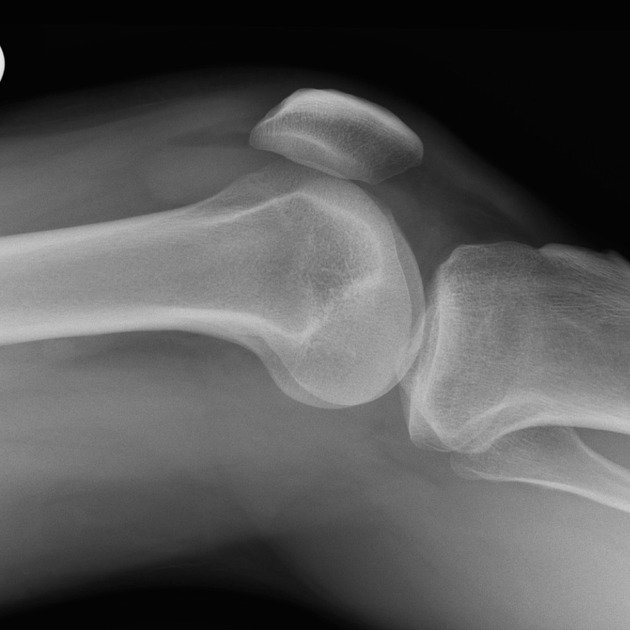

Knee Conditions GET IN TOUCH Knee Arthritis Meniscal Tears ACL Tears Knee Instability The Painful Or Failing Knee Replacement Knee Arthritis Learn MOre Meniscal Tears Learn MOre ACL Tears Learn MOre Knee Instability Learn MOre The Painful Or Failing Knee Replacement Learn MOre KNEE SURGERY OUR SERVICES If joint pain or injury is affecting your daily life, Dr Paterson is here to support your recovery with individualised, evidence-based care. Knee Arthritis Learn MOre Meniscal Tears Learn MOre ACL Tears Learn MOre Knee Instability Learn MOre The Painful Or Failing Knee Replacement Learn MOre OTHER TREATMENT OPTIONS